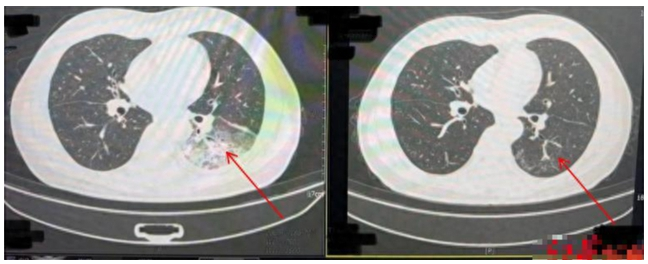

Kết quả chụp CT ngực cho thấy một nửa lá phổi trái của ông Lý trắng xóa. Kết quả nội soi rửa phế nang xác định ông Lý nhiễm vi khuẩn Legionella pneumophila gây viêm phổi.

Ảnh chụp CT trước khi điều trị cho thấy nửa lá phổi trái của ông Lý trắng xóa (bên trái) và ảnh chụp CT phổi sau khi điều trị khỏi (bên phải).